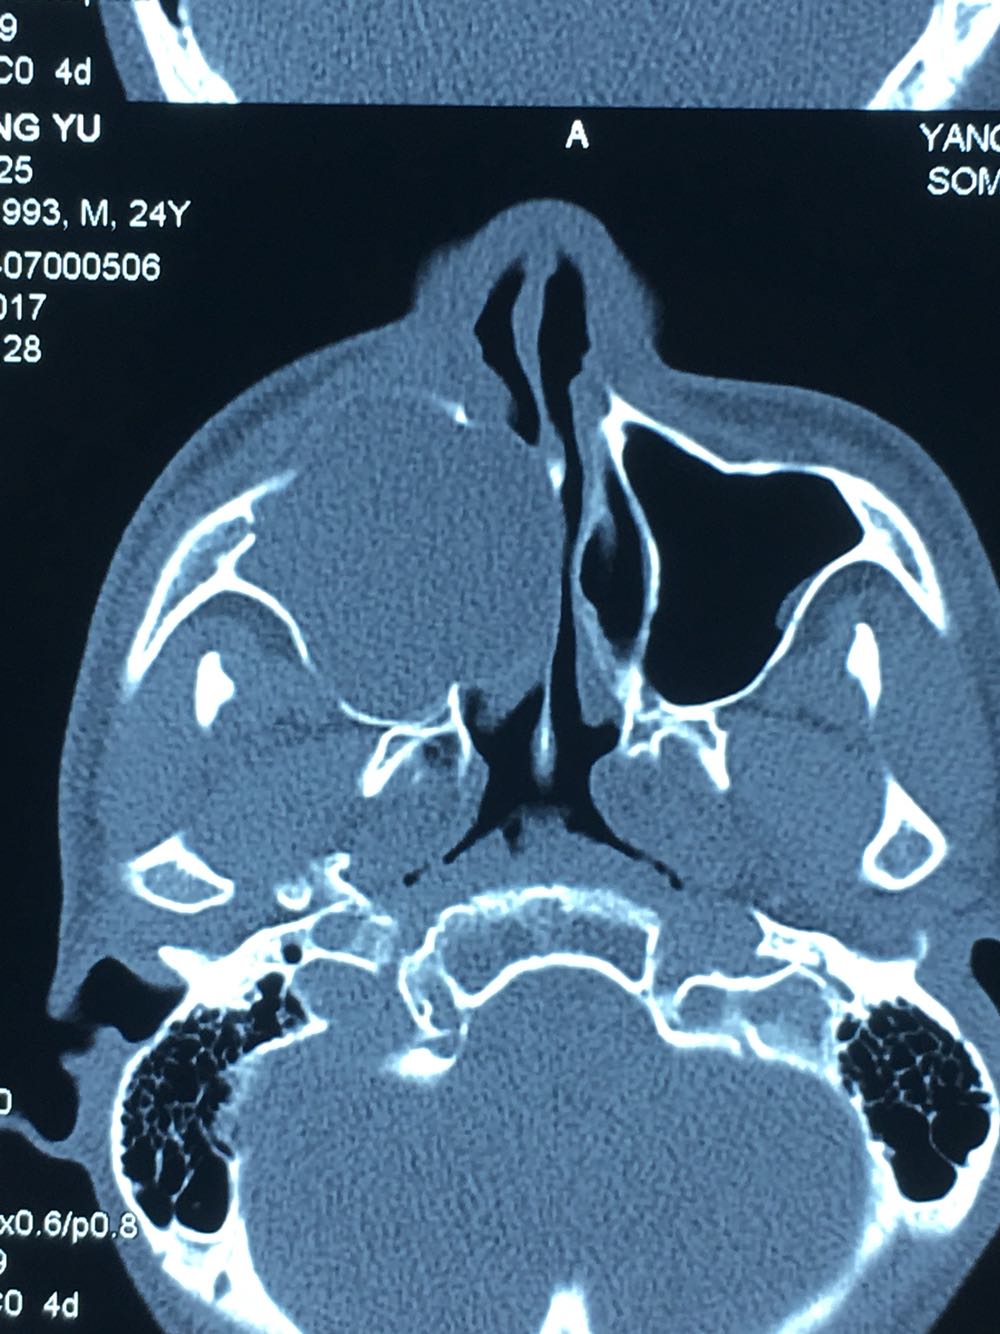

查体:面部明显不对称,右上颌膨隆明显,右鼻翼抬高,眶下区无麻木感,眼球运动自如,13牙齿缺如,16-22牙齿唇侧前庭肿胀,中央扪及波动感,边缘乒乓感,相关牙齿1度松动。 辅查:穿刺,抽得淡黄色液体,全景及CT,上颌骨囊肿,右侧上颌骨骨质大部分破坏

诊断:右上颌骨囊肿,13埋伏阻生。 治疗:开窗减压,拔除13阻生牙齿